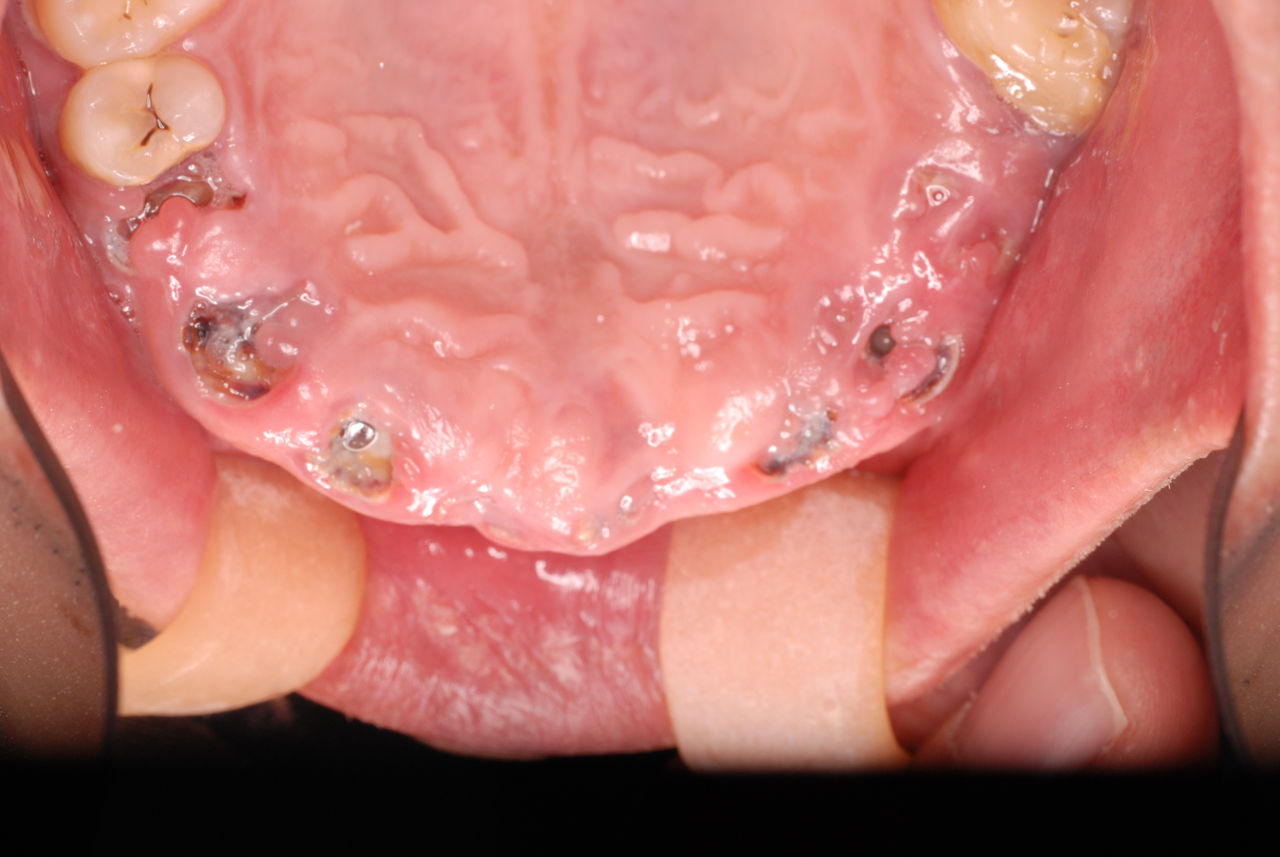

30代の男性の方です。

入れ歯を入れていました。歯科医院で歯を抜けず仕方なく入れ歯にしたとか。何とかならないものだったのか悔やまれました。

抜いた歯はありません。

一応差し歯にしましたが、歯茎の状態はよくはありません。

とりあえず希望を入れて差し歯にしたような感じです。